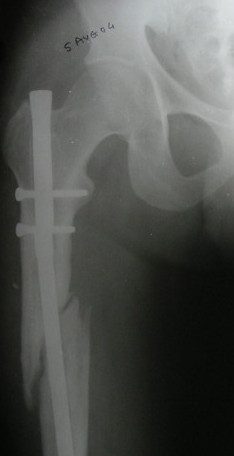

VMI> Kindly note. a) the nail is going towards the medial aspect

VMI> of the lower end thus causing a 5* varus at the # site. b) there

VMI> is a slight overiding causing a centimeter of shortening.

Such slight defomation must be possible to correct acutely using a distractor.

VMI> Implant removal may not be easy with the distal screw broken and

VMI> the nail broken too.

Exactly. We removed recently such a distal part of a hollow nail using a guide pin inserted from the knee through the stab wound. The hole in the notch was made by a cannulated awl. Then the pin passed to the proximal end of the femur, and a cannulated nail inserted to push the broken part distally over the guide pin. There is a set for broken

nail removal.

My final plan is as follows:

Remove the implant. (taking all sort of precautions and preparations). The fracture will not disengage or disimpact. Introduce a beaded guide wire. While entering the distal fragment, I will try to guide it more laterally (and not in the same earlier track) by using one or two Poller screws (pins) to be in the center of the medullary cavity, ream up to 12mm or more if possible, introduce an Indian ss nail (of which I am confident) size 1 mm less than what I have reamed, and lock with one proximal and 2 distal bolts. This nail if it has entered properly the way it was meant to be some correction of the angulation would have taken place. Weight bearing as soon as the patient can. Wish me all luck.